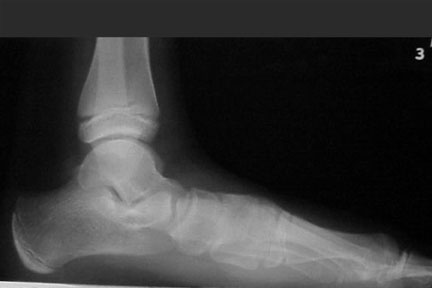

Sagittal plane deformities. A line bisecting the talus on the lateral radiograph should continue distally and downward so it parallels the first metatarsal shaft. If it does this, the navicular and the first cuneiform are presumably in line as well. If it does not, then there is sagittal failure somewhere along the medial column.

This failure can occur at the talonavicular joint, the cuneonavicular joint, the first metatarsocuneiform joint or in several of these areas at the same time. This failure results in the familiar “fault.” When this occurs, the talus goes into obligatory plantarflexion and the ankle goes into some degree of equinus position. The result is a plantigrade medial side of the foot. The sagittal failure can be flexible or rigid. When it is flexible, it is referred to as forefoot supinatus. When it is rigid, it becomes irreducible forefoot varus. The effect on subtalar range of motion varies from case to case but generally requires subtalar pronation to get the medial column down to the weightbearing surface.

Standing AP radiographs show the AP talocalcaneal angle is preserved. The lateral radiograph shows marked medial column collapse.

Presumably, the patient is fully pronated in stance and gait. Pain is limited to the talonavicular, calcaneocuboid and sinus tarsi areas. The therapeutic goals are control of the excess pronation and accommodation of the forefoot varus. The deformity dominates in the sagittal plane. Its rigidity limits orthotic therapy to support. One can try a partially pronated device with accommodation for part of the forefoot varus. Physicians should also consider surgical options.